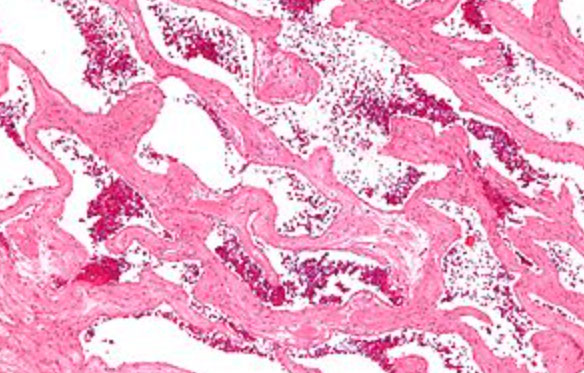

Micro: hepatic parenchyma with diffuse nodularity from small atrophic hepatocytes in zone 3, with normal to slightly big zone 1 and 2 hepatocytes, which is highlighted c reticulin stain

nodular regenerative hyperplasia with regenerative nodule (white arrow) bordered by irregular aligned small-sized hepatic trabeculae (black arrows)

nodular appearance of liver parenchyma (white arrows) characteristic of nodular regenerative hyperplasia. Areas with sinusoidal congestion are also present (black arrow